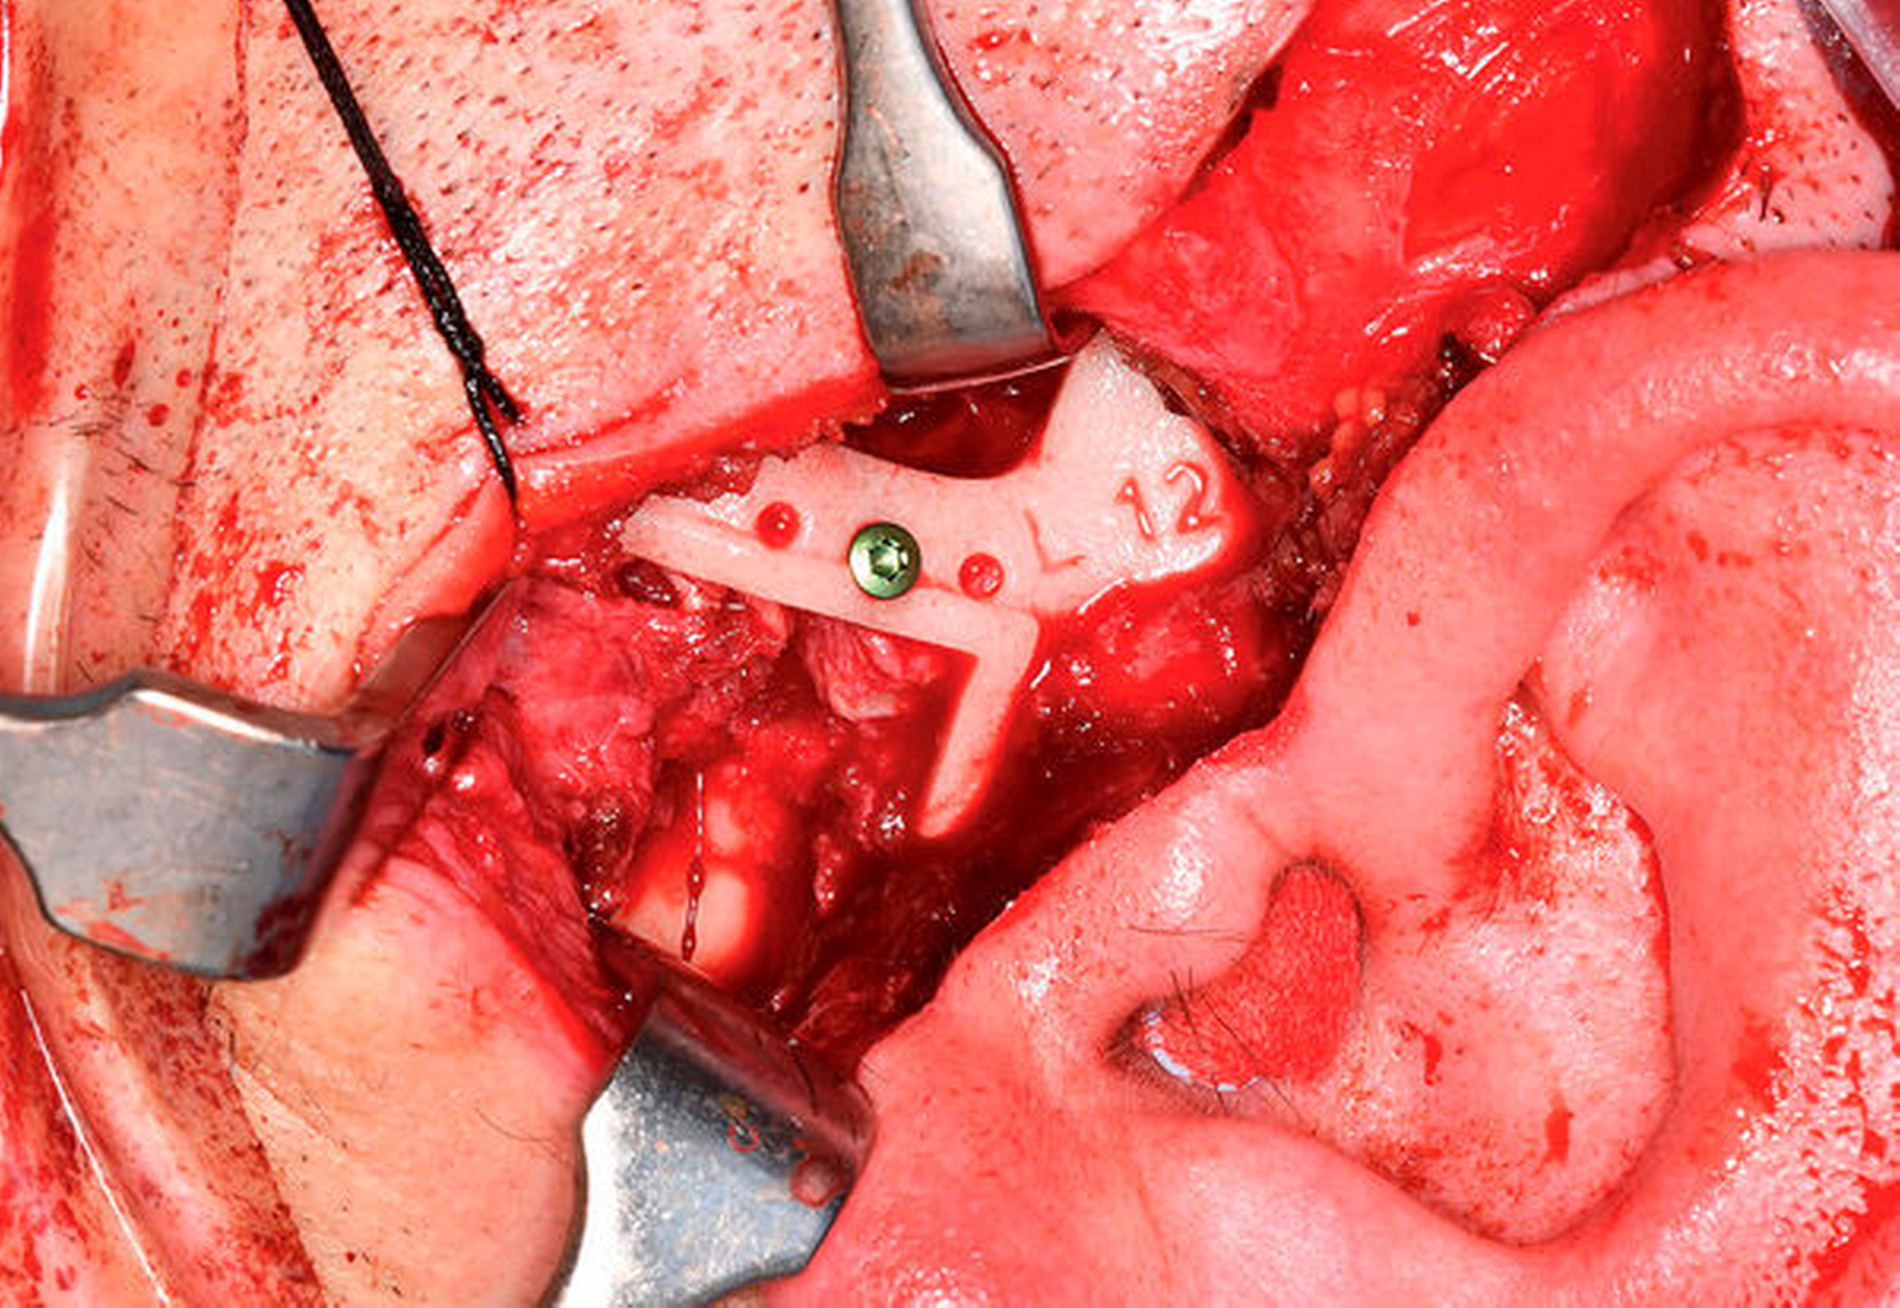

Danach erfolgte die beidseitige Abtragung der Ankylosemasse und die Resektion der deformierten Kiefergelenke mit modellierender Glättung der Jochbogenunterseite zur Schaffung einer Anlagefläche für die anschließend eingebrachten Fossakomponenten (Zimmer Biomet Holdings, Warsaw, Indiana, USA) (Abbildung 5). Nach Eingliederung der Unterkiefer-Intermediatprothese sowie des Zielokklusionssplints konnten die patientenspezifischen Kiefergelenk-Endoprothesen (Zimmer Biomet Holdings, Warsaw, Indiana, USA) (Abbildung 6) problemlos eingebracht und mit Osteosyntheseschrauben am ortsständigen Unterkiefer fixiert werden.